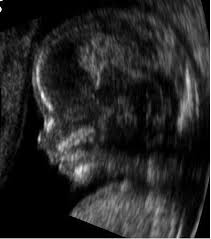

الفحوصـــــات الطبية :..

حيث تستخدم الموجات فوق السمعية فى تحديد نوع جنس الجنين ( علل )

حـ - وذلك اعتمادا على اختلاف أجزاء الجسم فى قدرتها على عكس الموجات فوق السمعية